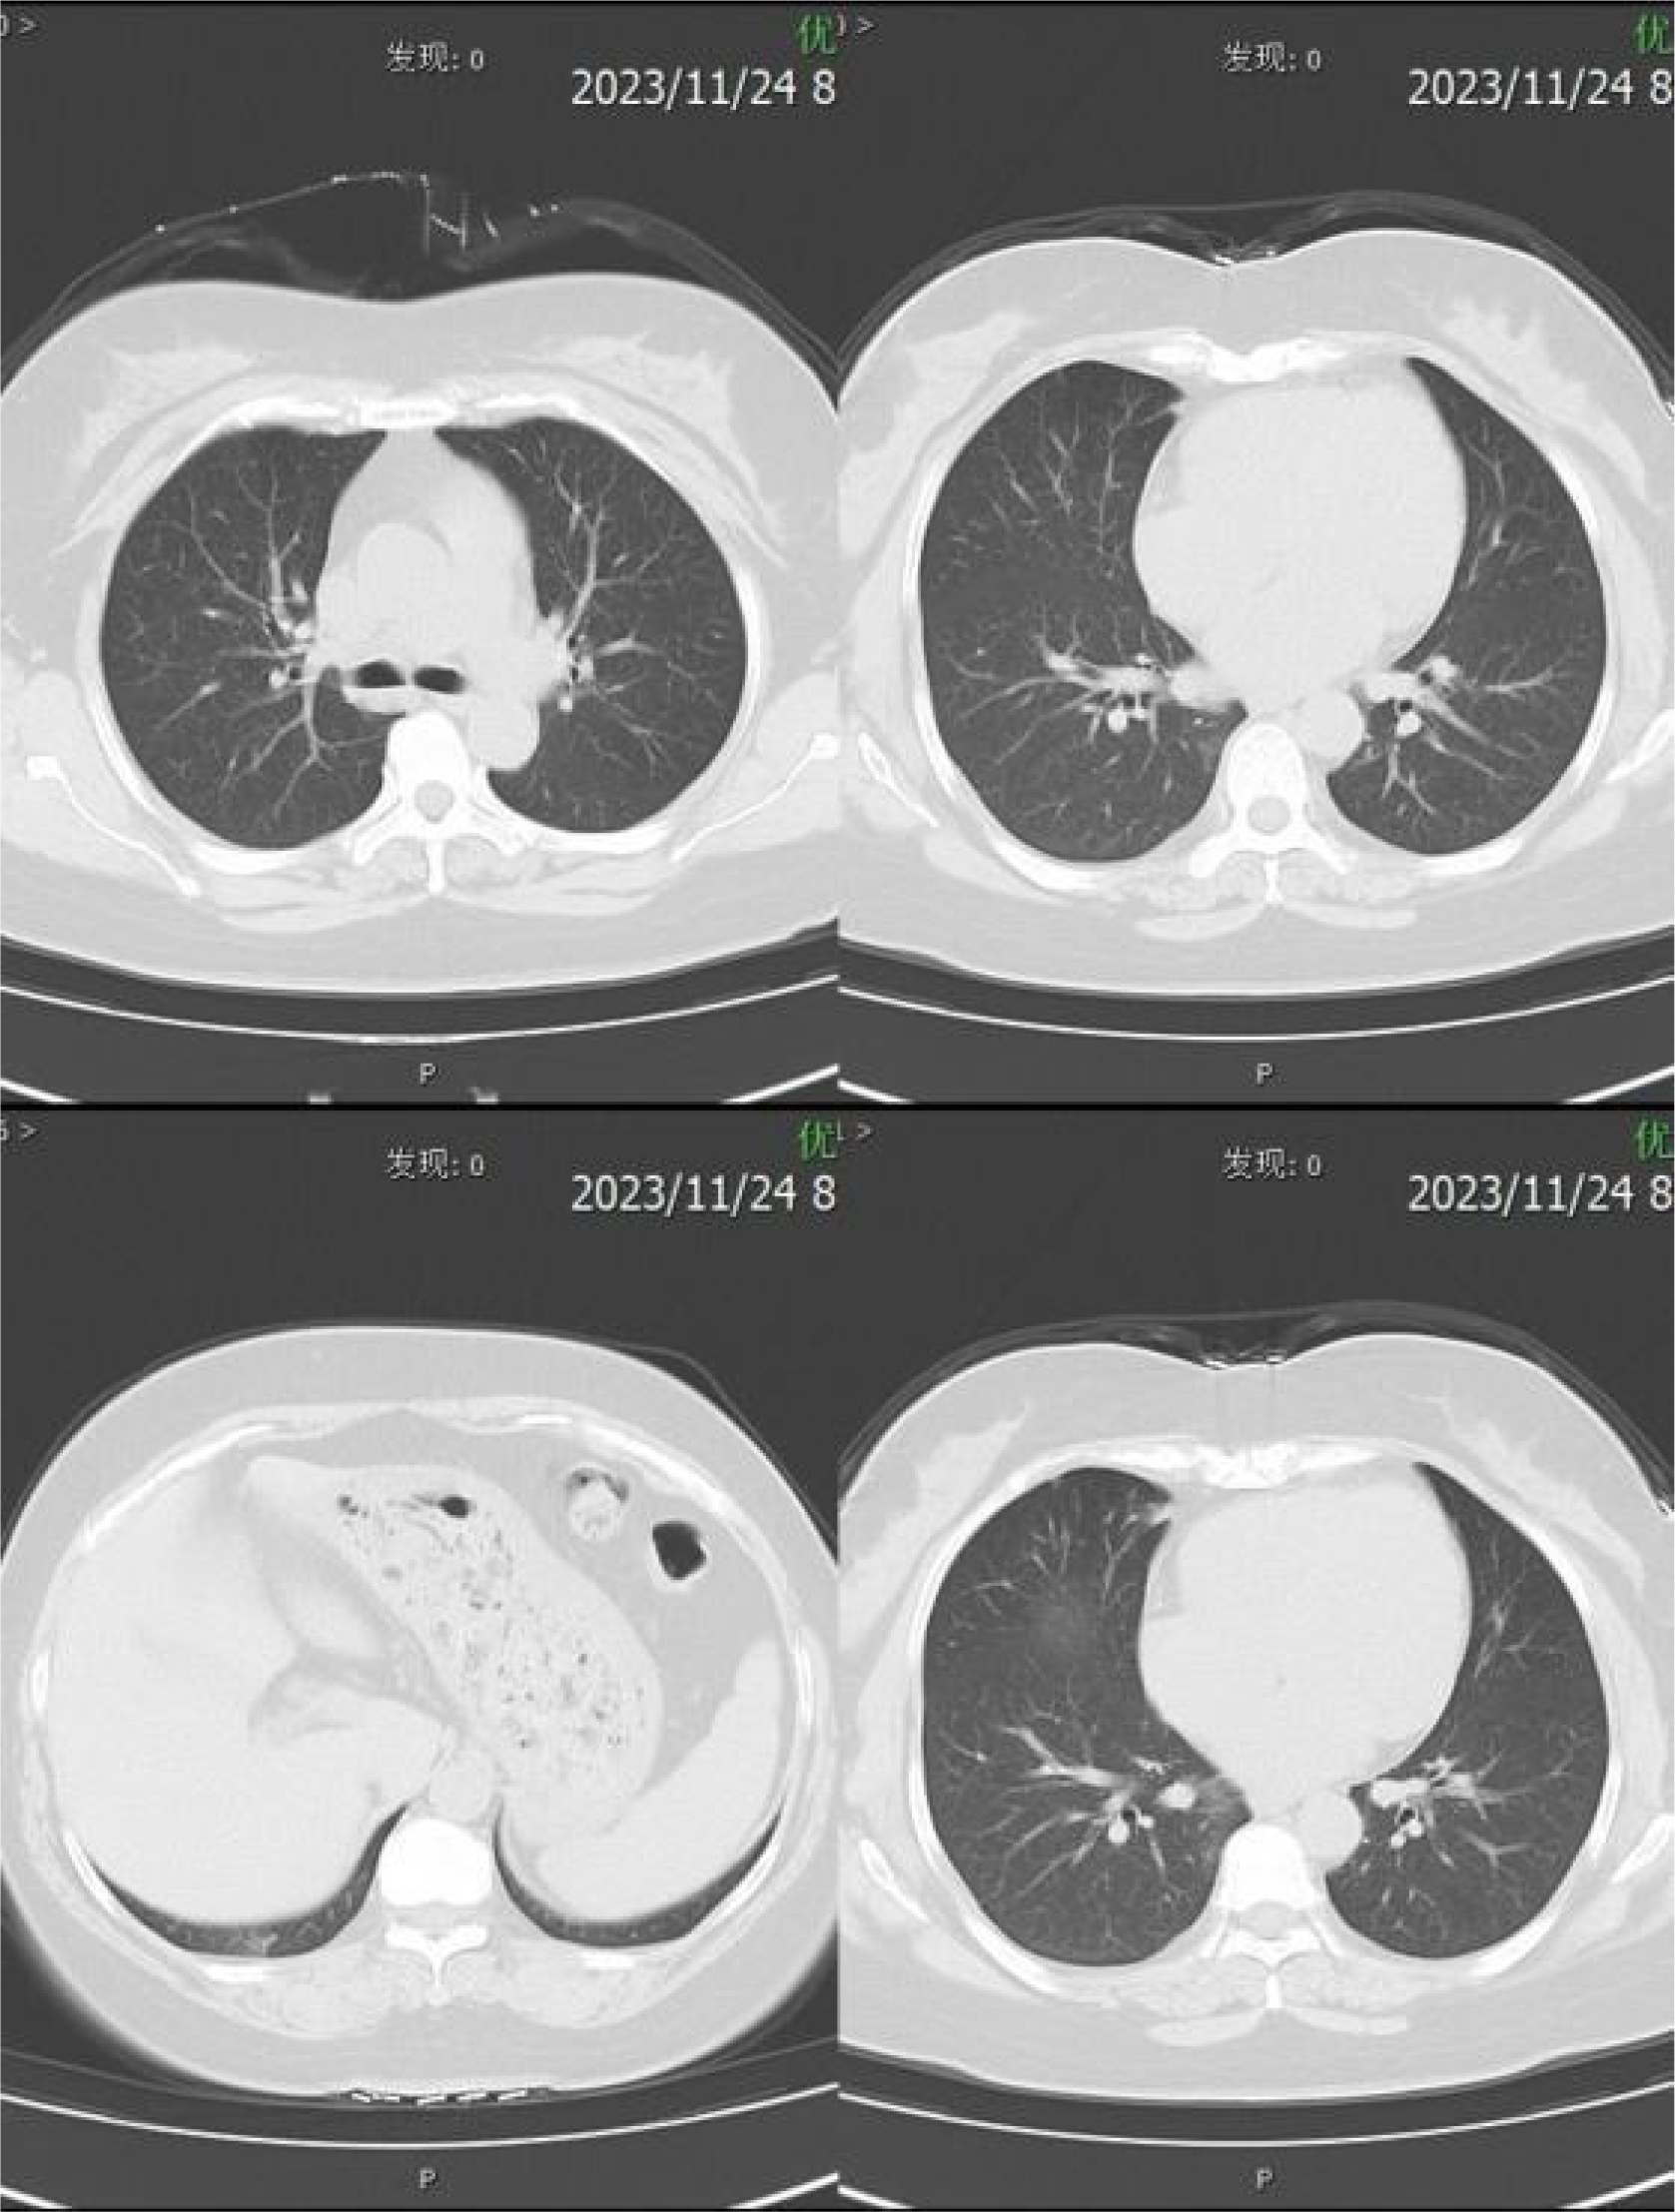

Relevant assistant examinations upon admission: no obvious abnormalities in hepatitis C, syphilis, HIV, liver function, myocardial enzyme spectrum, electrolytes, kidney function, and five items of coagulation; blood routine showed a white blood cell (WBC) count of 10.04×10^9/L and lymphocytes count of 3.51×10^ 9/L. Lumbar puncture demonstrated a CSF (colorless and clear) pressure of 120 mmH20, WBC count of 4×10^6/L and WBC may present occasionally in urinalysis; immunoglobulins: IgAC 8.12mg/L, IgGGC 66.00mg/L, IgMC 1.98mg/L and protein concentration 0.60g/L; and no obvious abnormalities in ink staining, fungal smear, acid-fast bacilli test, TORCH-IgM/IgG, and detection of Cryptococcus neoformans antigens. Nerve conduction study (NCS) showed incomplete bilateral facial palsy and no obvious peripheral neuropathy. Twelve antibodies of peripheral serum gangliosides tested negative. Chest CT scan showed slight inflammation in lungs, a few nodules in lungs, calcification in the left lung, focal pleural thickening, and multiple calcifications in the liver (see Figure 2). Brain MRI scan + contrast-enhanced + MRV suggested a few ischemic degeneration lesions in the brain and slight inflammation in paranasal sinuses, but no orbital space-occupying lesions, cavernous fistula, or cerebral venous sinus thrombosis (CVST) were found (see Figure 3).

Figure 2

CT imaging of the chest.